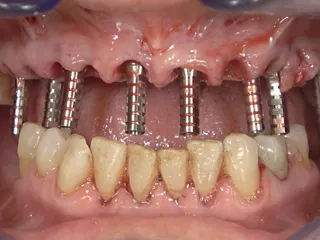

Guided FP1 maxillary rehabilitation with Straumann® STARconcept™ and Straumann iGuide™. A clinical case report by Dr. David Norré, Belgium.

Facially driven Smilecloud design with a focus on preserving tissue and bone. Planned in Smile in a Box and executed with the iGuide protocol; shared pin positions align the drill and prosthetic guides for chairside pickup of the pre-designed provisional. Day-5 follow-up shows the screw-retained provisional in place.

• Initial clinical situation (retracted view).

• Extraction of remanning teeth and placement of straight SRAs.

• Temporary Copings for SRAs placed – ready for bridge pick-up.